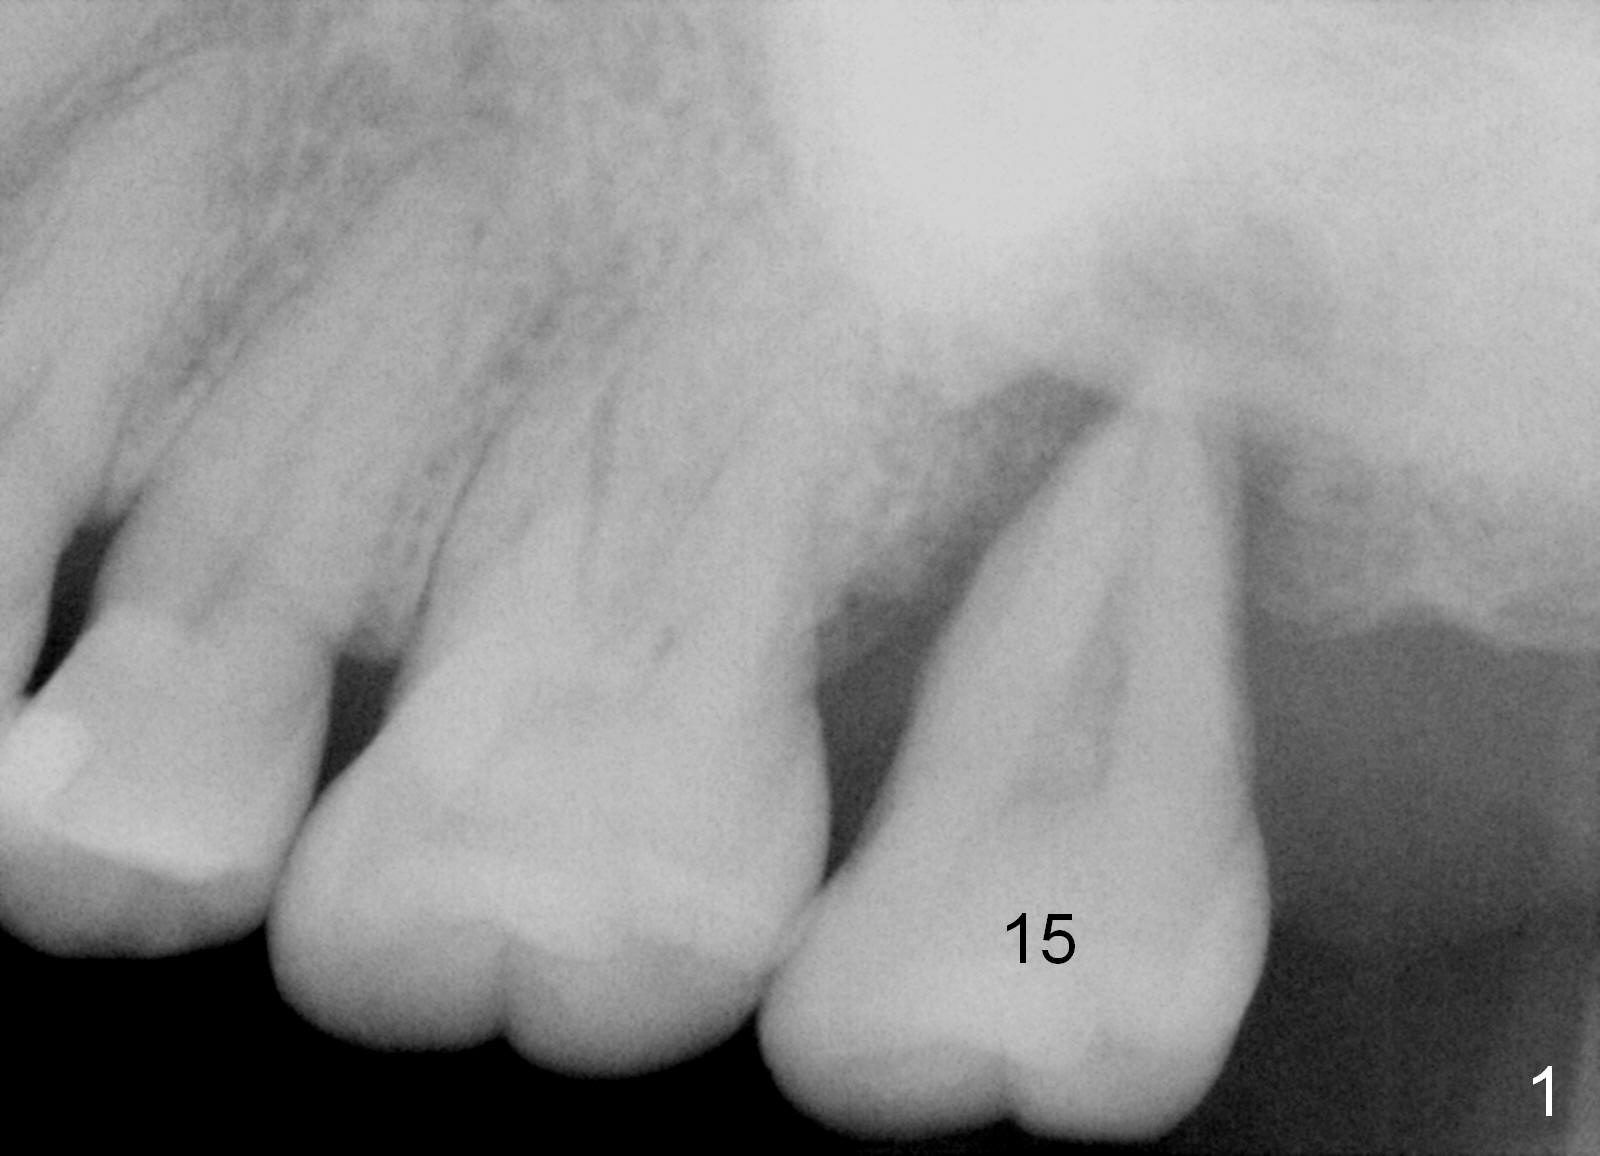

A 49-year-old lady has history of periodontal disease (Fig.1). The teeth #2 and 19 have been extracted and replaced by immediate implants. When she returns, crown is going to be cemented at #19 and delayed implant will be placed at #15. The tooth was extracted 4.5 years ago. No PA has been taken since extraction. Fig.2,3 show design for immediate implant if the tooth were not extracted (*: mesial crest; O: bone graft). Note the orientation of the implant and the space from the neighboring tooth.